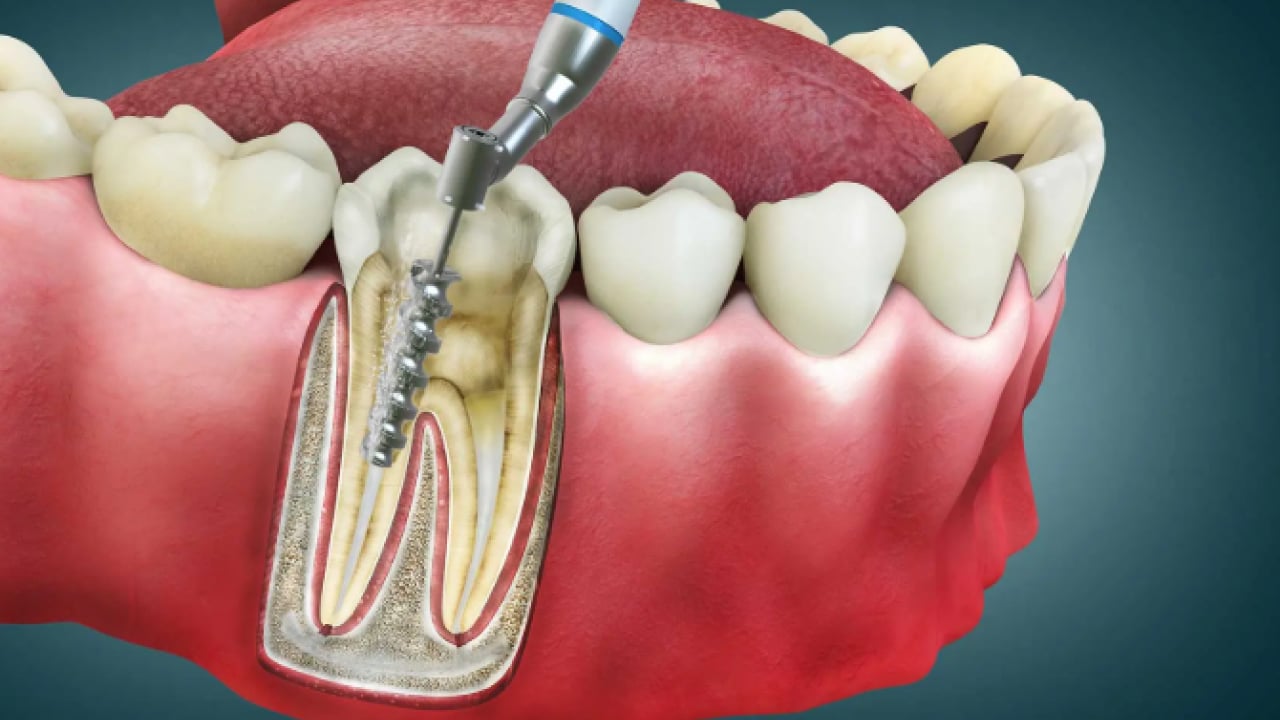

Dr. Öğr. Üyesi Sezer, "Dişin kök kanallarındaki sinir ve damar dokusu temizlenir, kanal duvarları arındırılır ve uygun materyallerle doldurularak diş restore edilir. Geçmeyen zonklayıcı ağrılar, gece uykudan uyandıran şiddetli ağrı, yüzde şişlik oluşturan apse, yemek yerken sıcakla veya dişe bastırınca oluşan hassasiyet gibi durumlar kanal tedavisi gerekliliğini düşündürür" diye konuştu.

“TEDAVİ SÜRECİ” Kanal tedavisi genellikle tek seansta tamamlanabilen bir işlem olduğunu anlatan Dr. Öğr. Sezer, "Ancak tedavinin durumuna göre bu süreci birden fazla seansa bölmemiz de gerekebilir. Bazen enfeksiyon yükü fazla olan yahut yüzde şişlik ile gelen hastalarımızda kanal içerisine ilaç uygulaması yapıp ilacın 1 hafta kadar dişin içerisinde durup etkinliğini göstermesini bekliyoruz. Bazı dişlerde ise ilaç uygulamadan, kanal içini temizleyip duvarları tamamen arındırdıktan sonra hemen dolguya geçebiliyoruz. Bu tamamen dişin durumuna ve iltihabın kontrol altına alınıp alınmadığına bağlıdır. Özetle, dişin genel durumu bizi yönlendiriyor ve bazen tek, bazen birden fazla seansla tedaviyi tamamlıyoruz. En sonunda dişe kalıcı restorasyonu yaparak süreci bitiriyoruz" diye konuştu.